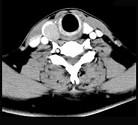

问题 男,43岁,因右颈部扪及一包块来院就诊。如图所示该患者应诊断为()

选项 A.甲状腺腺瘤 B.甲状腺腺癌 C.结节性甲状腺肿 D.甲状腺原发淋巴瘤 E.甲状腺转移瘤

答案 A